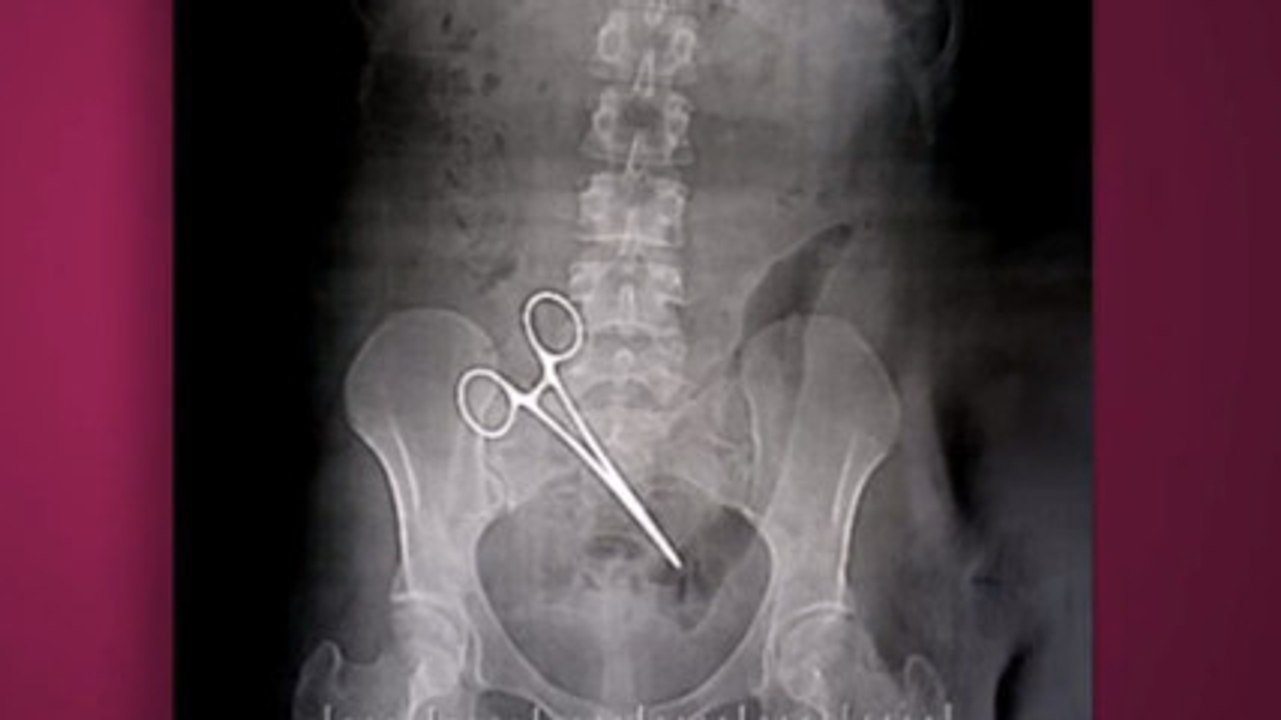

Suite à une opération, une jeune femme passe 5 mois avec une pince de 15 cm dans le ventre 1:12

Suite à une opération, une jeune femme passe 5 mois ave...